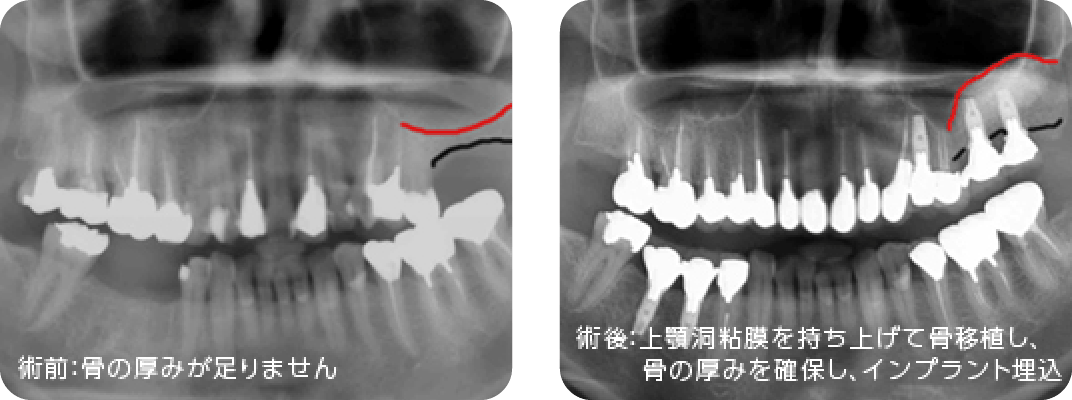

骨造成術

インプラントを埋入するだけの骨がない場合に異種他家骨※1や自家骨※2を移植しインプラントを埋入できるようにします。インプラント埋入と同時に行う場合と、インプラント埋入前に行う場合があります。

ソケットリフトとサイナスリフト

上顎臼歯部には上顎洞(副鼻腔の一つ)が存在し、骨の高さが足りない場合があります。その場合、上顎洞底部の洞粘膜(シュナイダー膜)を挙上し、挙上によってできた空隙に骨移植を行い骨造成し、インプラントが埋入できるようにします。当院では骨の高さが5~6mm以上の場合にソケットリフト、5~6mm未満の場合にサイナスリフトを行います。つまり、たくさんの骨移植が必要な場合にはサイナスリフトになります。